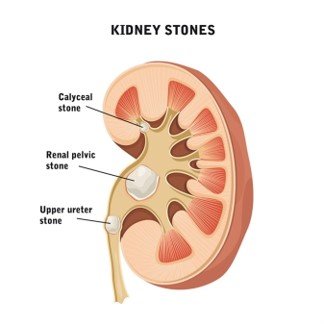

Key Imaging Findings:

- Renal or ureteric calculus appears as a hyperdense focus (usually >200 HU).

- Detects stones as small as 1–2 mm.

- Precisely defines size, number, and exact location.

- Common sites of impaction: PUJ, iliac crossing, VUJ.

Key Imaging Findings:

- Hydronephrosis, hydroureter.

- Perinephric fat stranding (suggests acute obstruction).

- Delayed nephrogram(if contrast phase is done later).